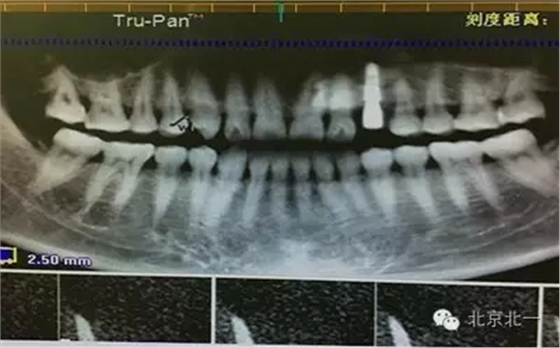

患者種植一月后種植區(qū)不適,偶有疼痛來(lái)院拍片發(fā)現(xiàn)23埋伏牙,與種植體相鄰,如圖一、二、三、四所示。